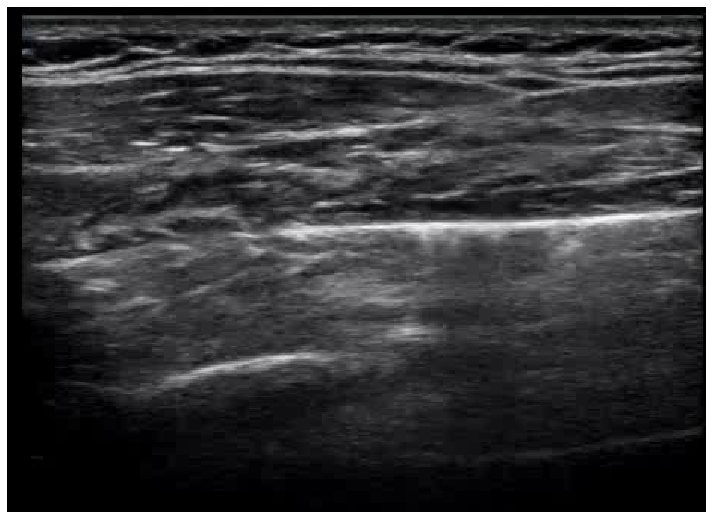

For example, POCUS images captured using a convex probe have a greater field-of-view with a cone shaped viewing window. This window differs in its viewing angle from device to device, and can also have a variety of forms as shown in Figure 1. In contrast, POCUS images captured using a linear probe has a more restricted field-of-view, but have a linear viewing window with visual content appearing distorted compared to that of images captured using a convex probe.